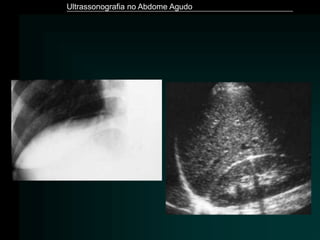

• Exames de imagem

– Radiografias (abdome e tórax)

– Tomografia Computadorizada

– Ultrassonografia

Ultrassonografia no AbdomeAgudo Pancreatite Aguda • Exames laboratoriais – Amilase – Lipase – Glicose – Cálcio – Leucograma – Gasometria arterial • Exames de imagem – Radiografias (abdome e tórax) – Tomografia Computadorizada – Ultrassonografia